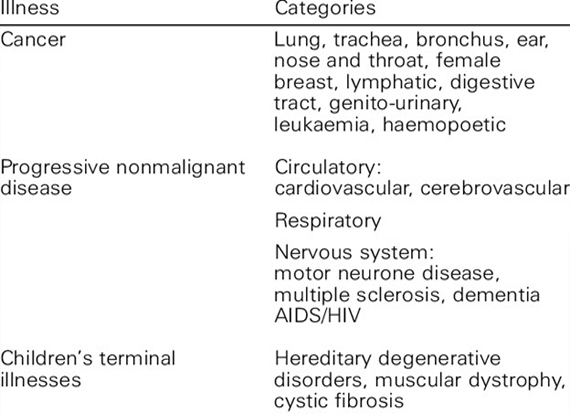

– Various cancers

– Incurable terminal and Incurable diseases.